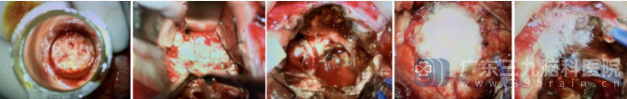

时间就是生命。神经外五科团队紧急启动多学科协作预案,联合影像科、呼吸内科、麻醉科等多个科室,在最短时间内完成了术前评估和准备。在全麻下,我们为患者实施了右侧颞枕叶-脑室后角转移瘤切除术+脑室外引流术,成功切除了颅内的转移灶,解除了脑疝风险,为后续治疗抢出了宝贵的时间窗口。

病理报告:(右颞叶脑室枕角肿瘤)脑转移癌,结合病史及免疫组化结果,支持为转移性肺腺癌。